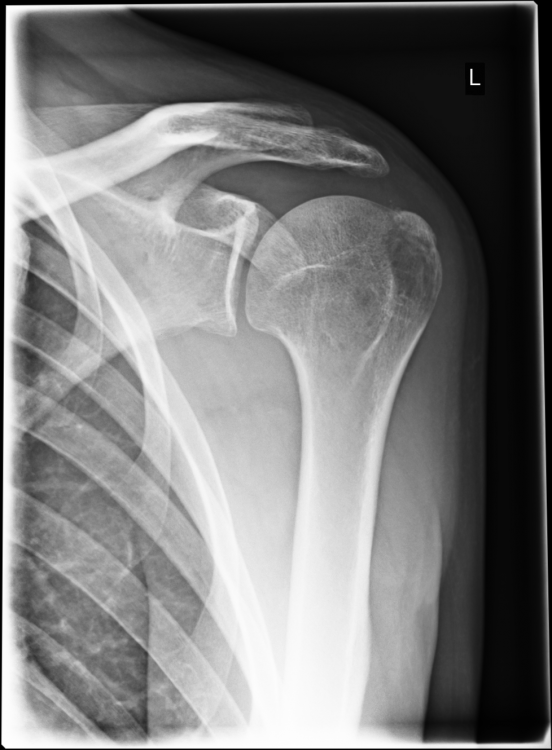

3. Röntgen am Unfalltag: --- MRT nach 6 Wochen (die Bilder habe ich selbst am PC gemacht - mein Arzt hat sie mir vorher gezeigt): --- Röntgen nach 12 Wochen: